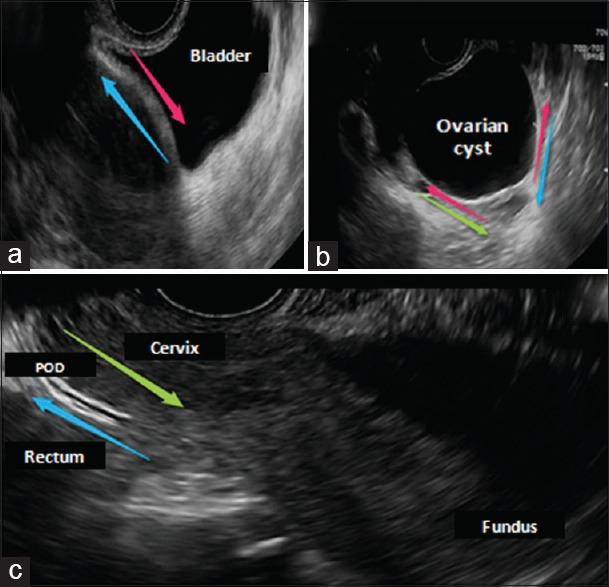

Ultrasound detection of the "sliding viscera" sign promotes safer laparoscopy.